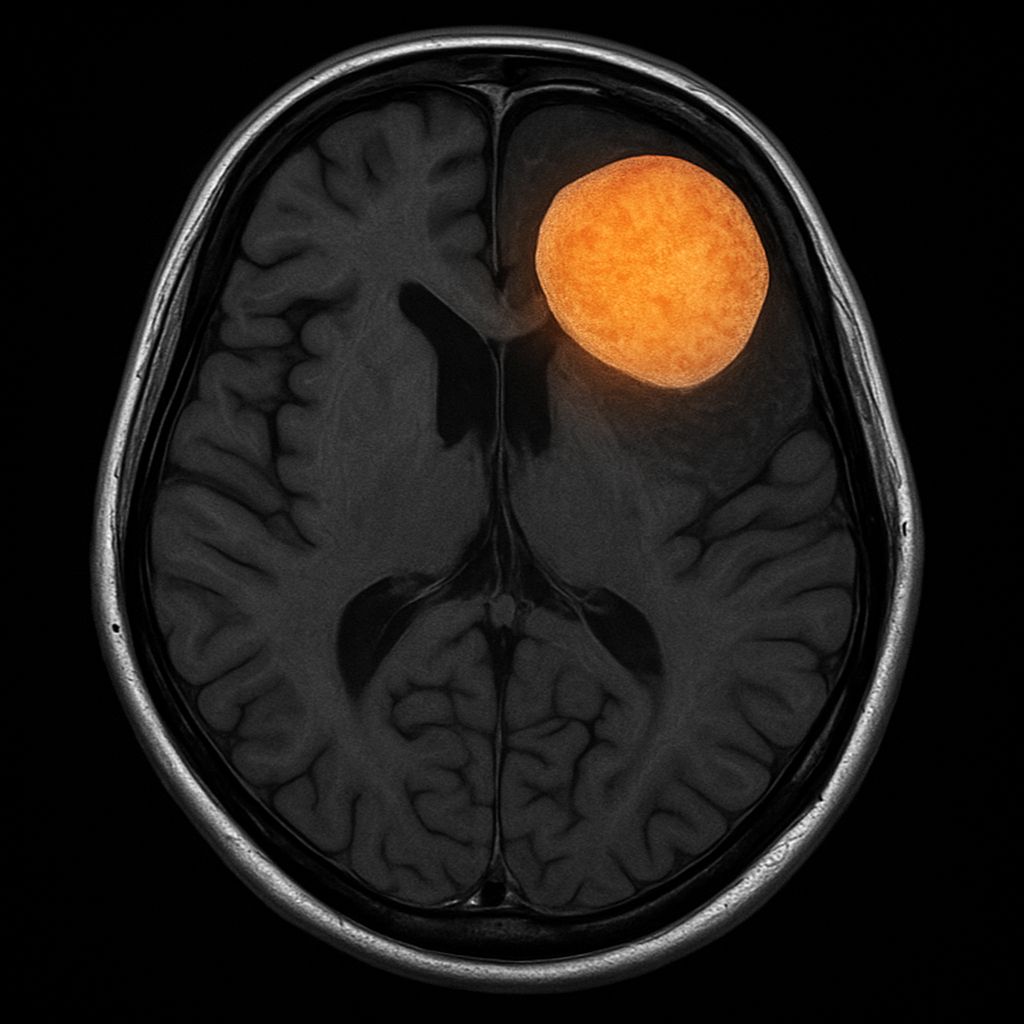

MRI of the spine may show gadolinium enhancement of nerve roots, particularly in the cauda equina.